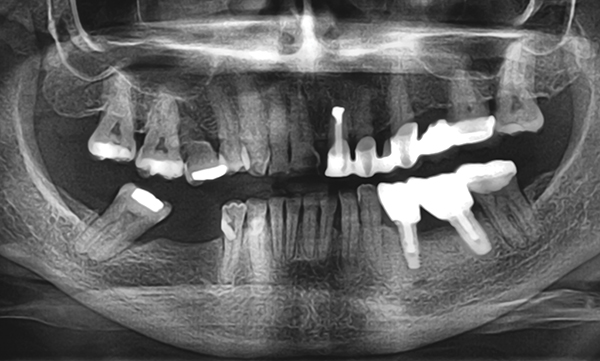

O 29 mm 1 o 33 mm 2 o 41 mm 2 o 48 mm. Straumannbone level tapered blt soft bone hard bone mandible in densifying mode make sure your osteotomy is 10 mm deeper than the actual implant final length. The straumann bone level tapered blt implant offers all the clinically proven features of the straumann bone level implant line plus the advantages of a tapered implant body. Implant blt straumann dental implant system.

Scs screwdrivers long and short 7. The straumann bone level implant line has a simple and consistent color coding and laser markings for quick and precise identification of secondary parts surgical instruments and auxiliaries. A unified color code simplifies identification of instruments and implants for the available endosteal diameters. 121 straumann standard implant the classic tissue level implant straumann standard implants have a smooth neck section of 28 mm and are especially suitable for classic.

The straumann blx implants are made from the material roxolid with the slactive surface and are available in the endosteal diameters 35 mm to 65 mm with length options from 6 mm to 18 mm. Straumann smartone 31 impression taking with the sp rn implant open tray instrument set up for open tray impressions with sp rn implants. Light bodied impression material dispenser 3. Novaloc retention system bl blt.